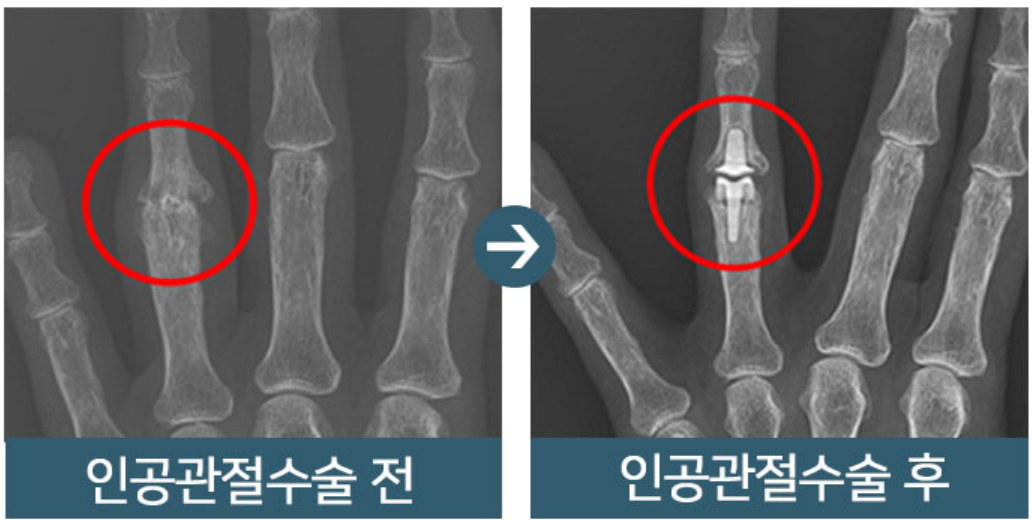

손가락 관절염 치료법

손가락 관절염 치료법은 직접적인 손가락에 시술을 하기 보다는 약물을 통한 염증 치료와 증상을 완화하는 형태의 치료로 진행됩니다. 다만 류마티스 관절염 같은 경우는 외과적인 치료가 아니라 면역계의 문제로 보기 때문에 스테로이드제를 동반한 치료가 진행되며 관절염으로 정형외과를 방문했더라도 차도가 없다면 류마티스로 특화된 류마티스 전문의를 만나 헐액검사를 포함한 전반적인 검사를 받는 것이 중요합니다.

또한 퇴행성 관절염인 경우에도 비수술적 치료를 진행하는 것이 필수적인데 관절 노화 외상이 이유가 되기 때문에 검사를 통해 약물 치료와 물리 치료로 우선 치료를 받고 통증이 가시지 않는다면 수술을 받아야 합니다. 하지만, 퇴행성 관절염의 경우 오랜 사용과 반복되는 부담으로 인하여 연골이 닳고 뼈가 변형이 이미 되어 있기 때문에 어떤 형태로 통증이 나타나느냐에 따라 다른 치료방식이 도입되는 것이 특징입니다.